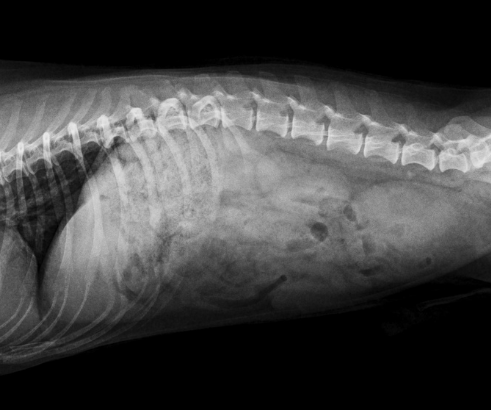

RX Espacios intervertebrales y componentes óseos de columna toracolumbar, lumbar y lumbosacra de aspecto radiográfico normal para la edad del paciente. No se observan signos radiográficos sugerentes de descoparías en las incidencias realizadas.

Ambas articulaciones coxofemorales de aspecto radiográfico normal y ambas rotulas en posición normal en las incidencias realizadas.